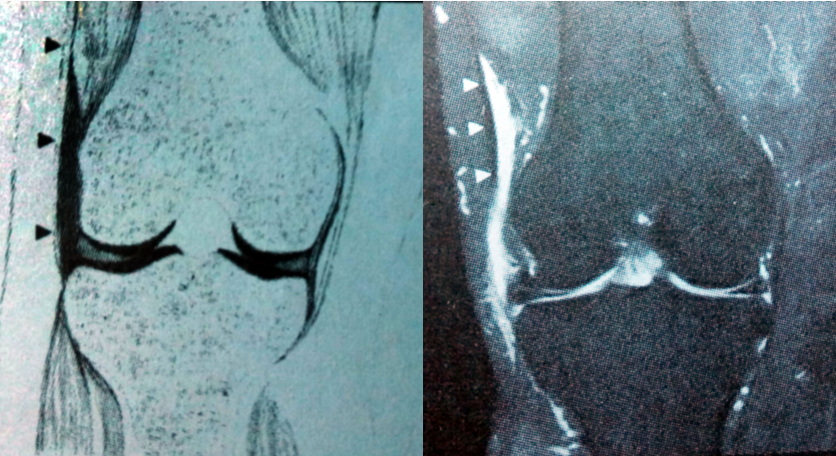

MRI表现

• 外侧半月板囊肿典型MRI表现为半月板撕裂附近的边界清楚的圆形囊肿,并见囊肿有连接部与半月板相连,可形成“吹气球征”(确诊的依据之一)。大部分伴有半月板水平撕裂和关节积液。半月板撕裂在T2WI上可看见半月板内高信号的液体;

• 在 T1WI上呈均匀的低信号,在 T2WI上呈均匀高信号。部分可见线条状低信号分隔;

• 但当半月板囊肿内有血性或凝胶状液体,蛋白含量增多时,在 T1WI 上信号强度可能有所变化,呈中等或高信号;

• 按其发生所在的部位分为半月板内型囊肿、半月板旁型囊肿、滑膜囊肿,以半月板旁型囊肿常见,发生于外侧半月板的囊肿较内侧半月板多。